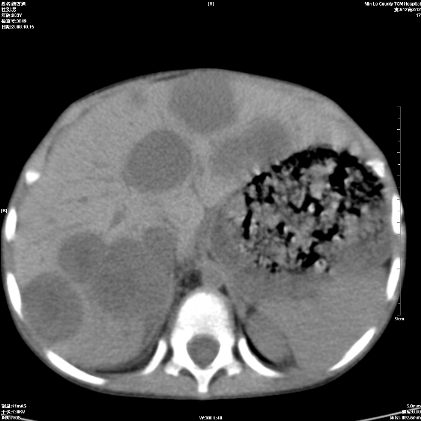

标题: PED1609:男性,3岁。彩超示肝Ca. [打印本页]

标题: PED1609:男性,3岁。彩超示肝Ca.

3岁;肝低密度灶;有钙化;有转移灶;考虑肝母细胞瘤;查afp

支持肝母细胞瘤肝内转移

考虑神经母细胞瘤并肝转移

考虑:1、右侧后下纵隔畸胎瘤。

2、肝脏多发血管内皮细胞瘤。

建议:增强确诊。